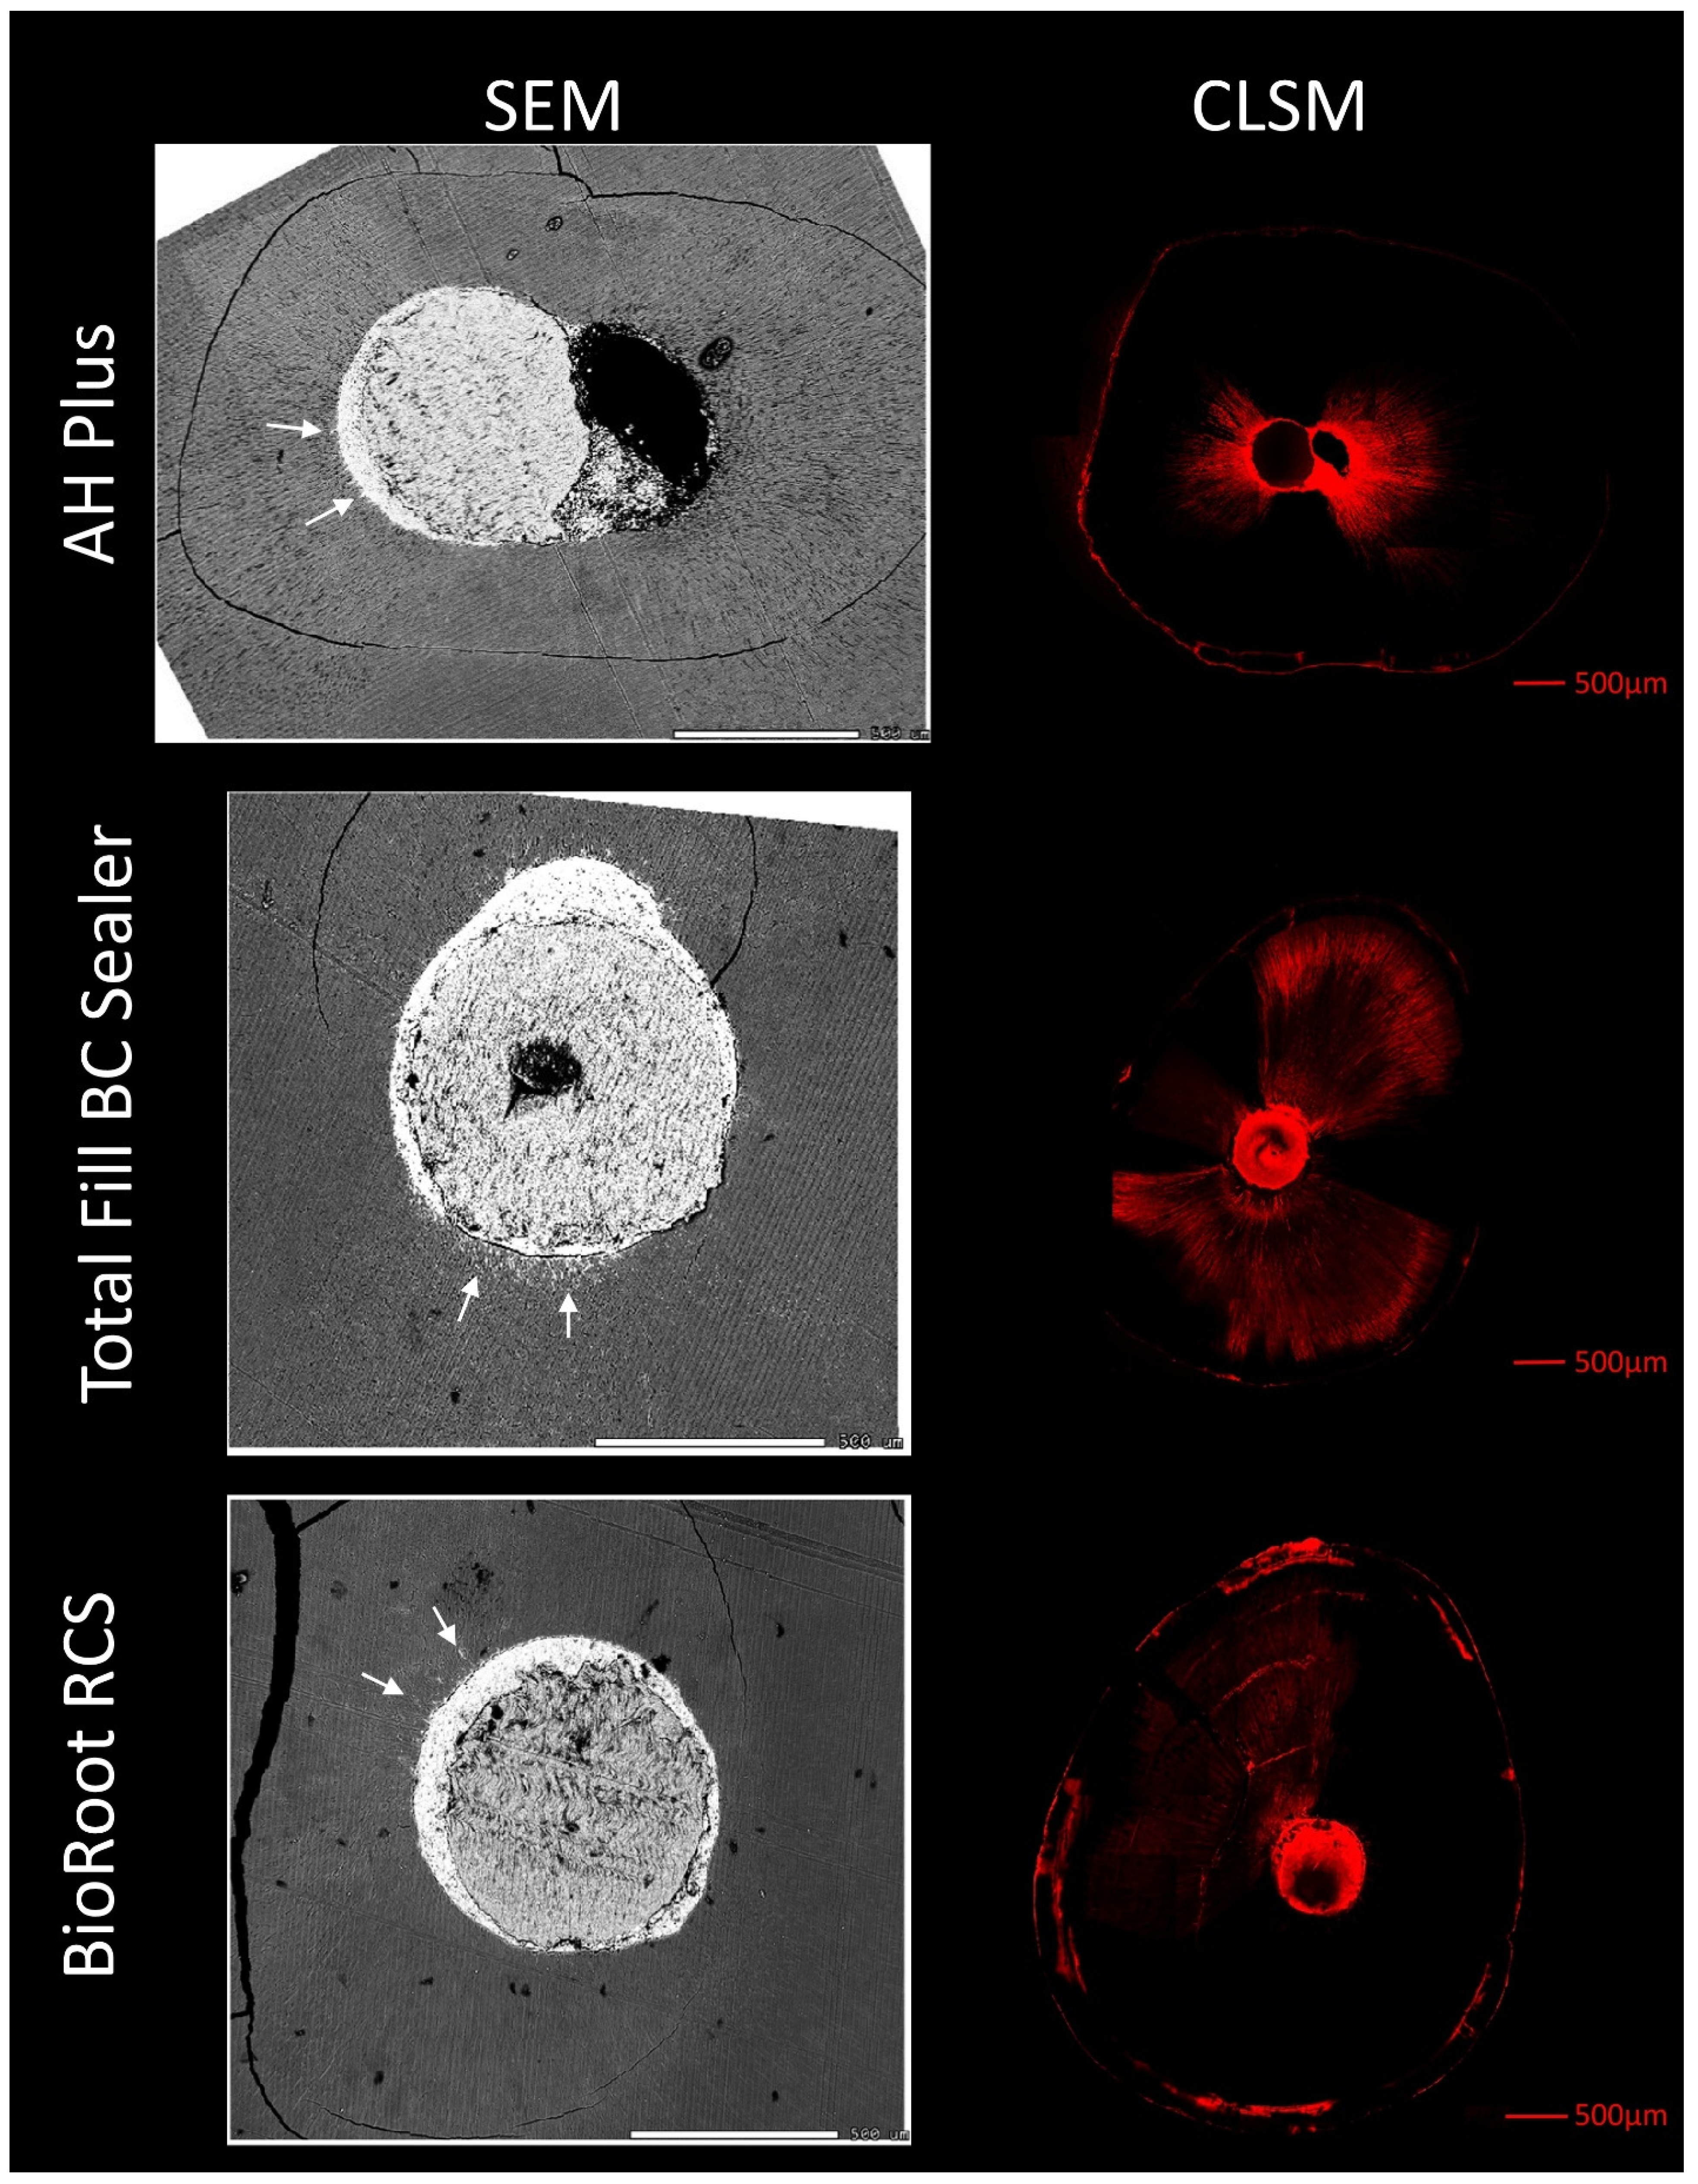

3. Results

3.1. Experimental Setup 1

3.2. Experimental Setup 2

3.3. Experimental Setup 3